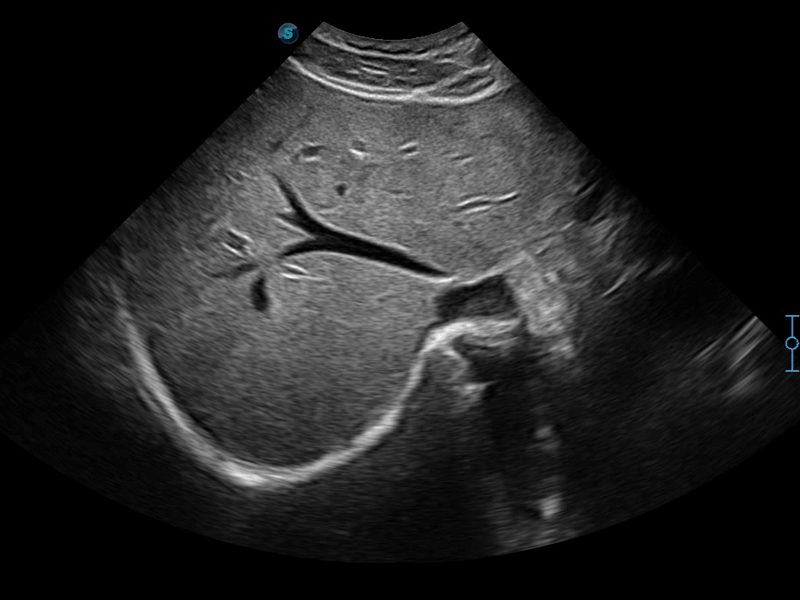

開立醫(yī)療通過不斷的技術(shù)創(chuàng)新,為大眾的生命健康提供持續(xù)關(guān)愛。P12 Plus采用全新一代超聲成像平臺,新平臺旨在將真實(shí)還原組織解剖結(jié)構(gòu)作為首要目標(biāo)。平臺采用全新集成化硬件模塊,搭載新一代芯片,系統(tǒng)性能得到大幅提升,為您的診斷提供了豐富的臨床信息。優(yōu)異的圖像表現(xiàn),豐富的探頭配置,全面的應(yīng)用功能,為您日常診斷提供了可靠的助手。

彩色多普勒超聲診斷系統(tǒng)